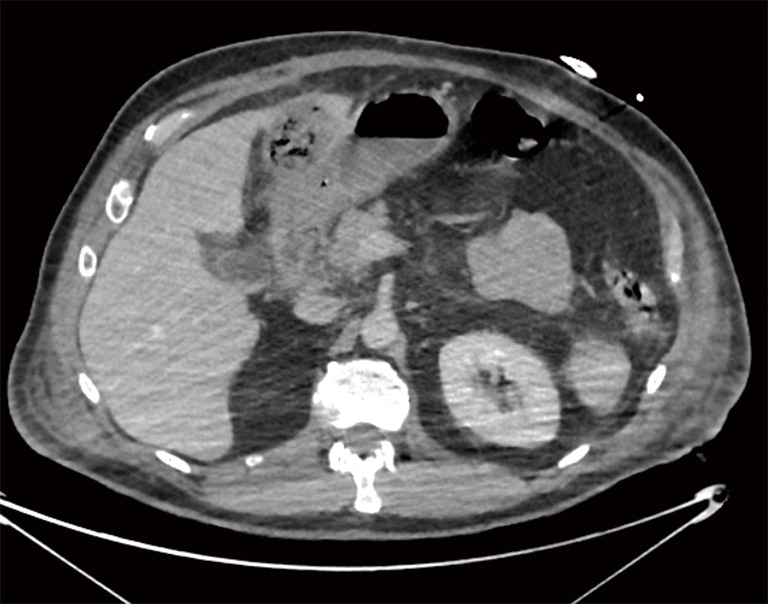

Case description: Here, we present a case of a 61-year-old male, admitted to emergencies with severe abdominal pain and one episode of vomiting. The patient initially diagnosed with mild acute pancreatitis and probable cholecystitis. Because of its severe clinical picture, the patient was admitted to our intensive car unit. Subsequent imaging revealed progression to gangrenous cholecystitis. Decision was taken to drain the gallbladder under computed tomography (CT) scan. Despite antibiotic therapy, the patient developed acute respiratory distress syndrome (ARDS), necessitating intubation. Upon stabilization, an exploratory laparoscopy revealed infected necrosis of the falciform ligament, prompting resection and drainage. Postoperatively, the patient presented a progressive clinical and biological amelioration. The drain was removed and the follow-up was uneventful. A laparoscopic cholecystectomy was scheduled 3 months later.